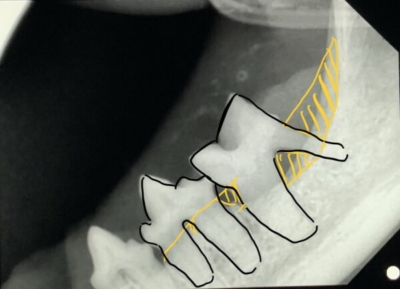

高齢猫ちゃんの歯肉口内炎

下顎のレントゲン写真

黄色矢印は歯周病(歯槽骨の拡大 )と吸収病巣で黒い隙間ができている犬歯の病変。口内炎でなくても抜歯対象。黒い囲みは吸収病巣で失われた歯があった部位。この部位の骨と一体化した歯根は可能な限り削る。